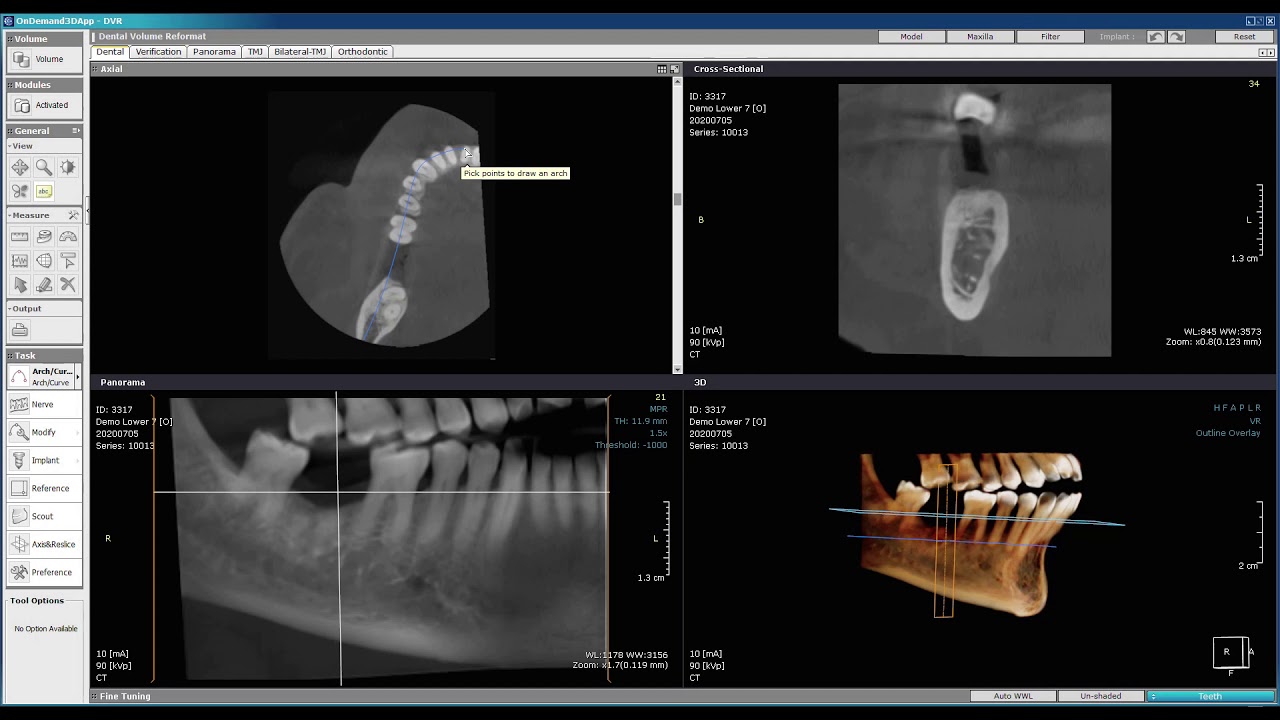

From sandiegoinvisaligndentist.org

How to read cbct for dental implants Dental News Network Dental Cbct Interpretation Find out how to select the. • describe dental scenarios as to when a cbct scan might be an imaging modality of choice. learn the general principles and protocols for analyzing cone beam computed tomography (cbct) scans in dentistry. learn how to interpret cbct scans for dental diagnosis and treatment planning from an oral and maxillofacial radiologist.. Dental Cbct Interpretation.